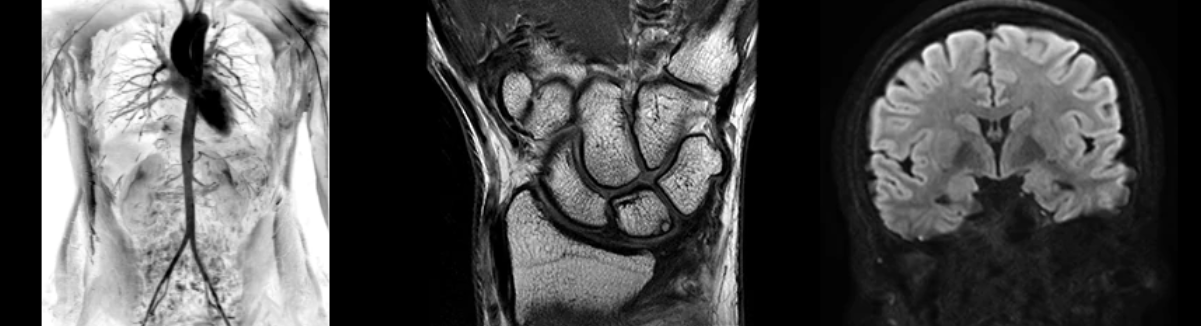

• NeuroWorks

Представляет собой универсальное решение для визуализации анатомии головного мозга, позвоночника, сосудов и периферических нервов с четкой дифференциацией тканей.

• OrthoWorks

Программное решение OrthoWorks разработано для визуализации структур опорно-двигательного аппарата с прекрасным контрастированием тканей.

• BodyWorks

Используйте BodyWorks для визуализации абдоминальной и тазовой областей с учетом любых типов пациентов.

• OncoWorks

Включает клинические приложения для обработки и визуализации анатомических и морфологических данных, специфичных для каждого типа онкологических образований.

•  CVWorks

Приложение для кардиовизуализации, с помощью которого вы сможете получить данные о морфологии, динамике кровотока, функции миокарда, а также информацию о структуре сосудов.